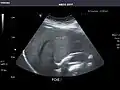

Liver: Diffusely homogeneous and normal in echogenicity. No focal mass or contour nodularity. No intrahepatic biliary ductal dilatation.

Portal Vein: Patent main portal vein.

Liver -